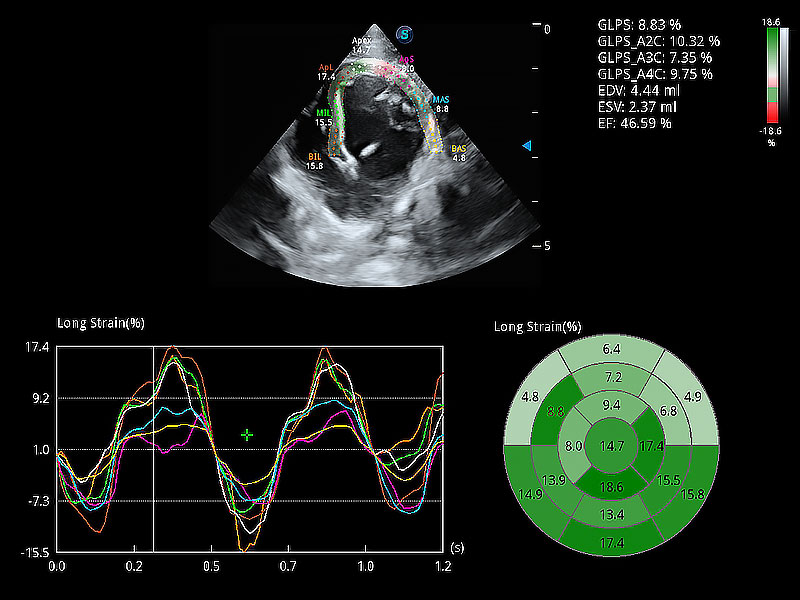

通過心肌識別技術(shù)與二維斑點追蹤技術(shù)相結(jié)合,對心臟的超聲圖像進(jìn)行量化分析。計算心肌17個節(jié)段的應(yīng)變、應(yīng)變率、速度、位移等,并通過牛眼圖的形式進(jìn)行呈現(xiàn)。

能夠基于左心室壁追蹤和辛普森法,自動計算射血分?jǐn)?shù),支持多個可移動點描跡,與手動測量相比,極大節(jié)省了動物醫(yī)生的時間和精力。